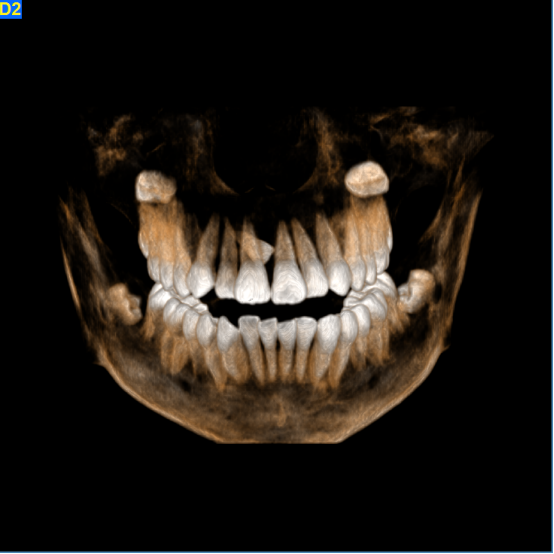

正畸通过扫描形成图像,包括曲面体层、头颅侧位进行测量图像。2D和3D图像在确定多生牙的存在及位置方面,有着巨大的差别。3D图像对扫描区域有着完整,综合的展示,甚至允许通过不同视角,以及对不同断面重建图像进行观察。